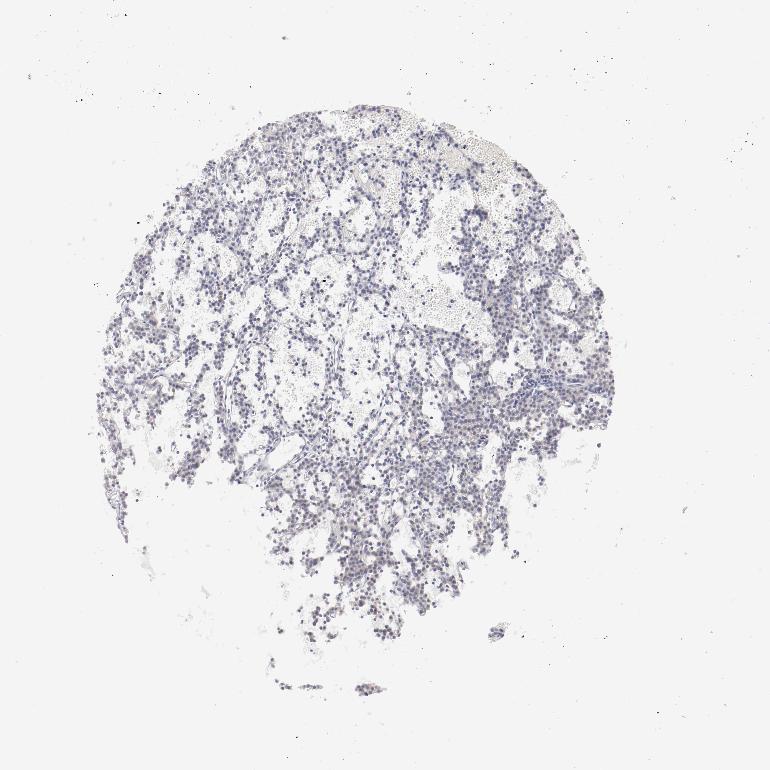

TISSUE PRIMARY DATA PARATHYROID GLAND Show tissue menu

PARATHYROID GLAND - Antibody stainingi

Antibody staining in the annotated cell types in the current human tissue is reported as not detected, low, medium, or high, based on conventional immunohistochemistry profiling in selected tissues. This score is based on the combination of the staining intensity and fraction of stained cells.

Each image is clickable and will lead to virtual microscopy that enables deeper exploration of all samples and also displays staining intensity scores, fraction scores and subcellular localization as well as patient and tissue information for each sample.

Antibody CAB003685

Glandular cells Not detected